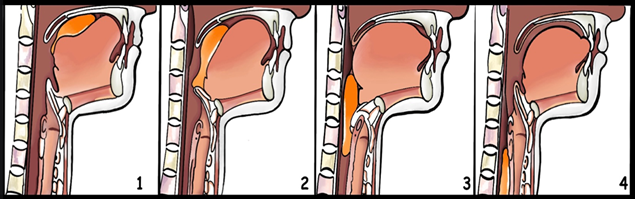

Определить уровень и механизм дисфагии достаточно трудно без знания анатомо-физиологических особенностей акта глотания, в котором выделяют четыре фазы [1] (рис.2).

Рис.2. Механизм физиологического акта глотания (фазы: 1 – ротовая фаза; 2 – ротоглоточная фаза; 3 – глоточная фаза; 4 – пищеводная фаза).

Примечание: составлен авторами по источнику [1]

Определение вида дисфагии имеет принципиальное значение для дальнейшей тактики лечения пациента. Рассмотрим особенности фаз глотания и клинические проявления у пациентов. Ротовая фаза осуществляется иннервацией из коры головного мозга предцентральной извилины при участии V, VII, XII пар черепных нервов. Клинические проявления нарушения на уровне этой фазы представлены следующими симптомами: дисфагия на уровне поражения ротовой полости и глотки, сложность начала глотания, удушье или кашель при глотании, слюнотечение, носовые срыгивания. Сопутствующие симптомы: «носовая речь» (назолалия), ослабленный кашлевой рефлекс, дизартрия или диплопия при взгляде. Ротоглоточная и глоточная фазы – это непроизвольный двигательный акт представлен врожденным (безусловным) рефлексом, который реализуется на уровне ствола головного мозга при участии V, IX, X, XI пар черепных нервов. Пищевой комок проходит через глотку за 0,3–0,5с, что является быстрой непроизвольной фазой. Клинические проявления этих фаз аналогичны ротовой. Пищеводная фаза – медленная непроизвольная фаза, непроизвольный двигательный акт. Осуществляется при участии Х пары черепных нервов, трех пар верхних шейных нервов. По пищеводу жидкость продвигается за 2–3с, пищевой комок – за 7–8с. При поражении на уровне пищевода дисфагия сопровождается ощущением «застревания» пищи за грудиной, ротовыми или носовыми срыгиваниями, необходимостью пациента запивать пищу.